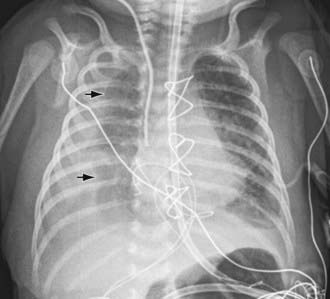

image

Figure 409-1 Chylothorax (arrows) following cardiac surgery in a 2 wk old infant.